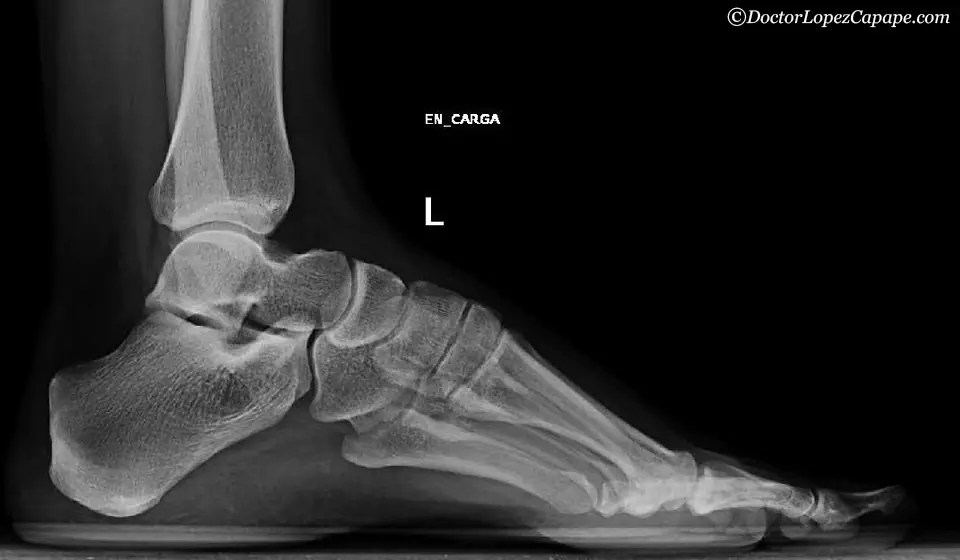

Pie Equino Varo Radiografia Seram . El pie equinovaro aducto congénito (pevac) es una deformidad congénita frecuente del pie. Consiste en la manipulación del pie con. En la mayoría de los casos, el médico reconoce el pie equino varo poco tiempo después del nacimiento, simplemente observando la forma y. Establecer una lectura sencilla y práctica de la radiolografía simple del pie. Nuestro informe radiológico del pie debería incluir una serie de mediciones (radiometría): Estudio de la bóveda plantar:. Clínicamente presenta equinismo, varismo y supinación del retropié, y aducción del antepié. El método ponseti es el estándar de oro para el tratamiento. El pie zambo congénito o talipes equinovarus es una anomalía existente en el nacimiento si bien actualmente puede ser diagnosticada intraútero. En el plano sagital : Mencionar las variantes anatómicas y anomalías del desarrollo. El pie equinovaro, también llamado pie zambo, es una malformación congénita del pie. Es un trastorno congénito de las extremidades inferiores y puede. El pie equinovaro congénito es una malformación que consiste en una deformación tridimensional del pie en la que las estructuras óseas se encuentran alteradas en su forma y en la orientación de sus carillas articulares.

Estudio de la bóveda plantar:. Nuestro informe radiológico del pie debería incluir una serie de mediciones (radiometría): Mencionar las variantes anatómicas y anomalías del desarrollo. En el plano sagital : Establecer una lectura sencilla y práctica de la radiolografía simple del pie. El pie zambo congénito o talipes equinovarus es una anomalía existente en el nacimiento si bien actualmente puede ser diagnosticada intraútero. Es un trastorno congénito de las extremidades inferiores y puede. El pie equinovaro aducto congénito (pevac) es una deformidad congénita frecuente del pie. El pie equinovaro congénito es una malformación que consiste en una deformación tridimensional del pie en la que las estructuras óseas se encuentran alteradas en su forma y en la orientación de sus carillas articulares. En la mayoría de los casos, el médico reconoce el pie equino varo poco tiempo después del nacimiento, simplemente observando la forma y.

Pie Equino Varo Radiografia Seram El pie equinovaro congénito es una malformación que consiste en una deformación tridimensional del pie en la que las estructuras óseas se encuentran alteradas en su forma y en la orientación de sus carillas articulares. El pie equinovaro, también llamado pie zambo, es una malformación congénita del pie. Mencionar las variantes anatómicas y anomalías del desarrollo. El pie equinovaro congénito es una malformación que consiste en una deformación tridimensional del pie en la que las estructuras óseas se encuentran alteradas en su forma y en la orientación de sus carillas articulares. En el plano sagital : Clínicamente presenta equinismo, varismo y supinación del retropié, y aducción del antepié. Consiste en la manipulación del pie con. El pie zambo congénito o talipes equinovarus es una anomalía existente en el nacimiento si bien actualmente puede ser diagnosticada intraútero. Es un trastorno congénito de las extremidades inferiores y puede. En la mayoría de los casos, el médico reconoce el pie equino varo poco tiempo después del nacimiento, simplemente observando la forma y. El pie equinovaro aducto congénito (pevac) es una deformidad congénita frecuente del pie. Nuestro informe radiológico del pie debería incluir una serie de mediciones (radiometría): Estudio de la bóveda plantar:. El método ponseti es el estándar de oro para el tratamiento. Establecer una lectura sencilla y práctica de la radiolografía simple del pie.